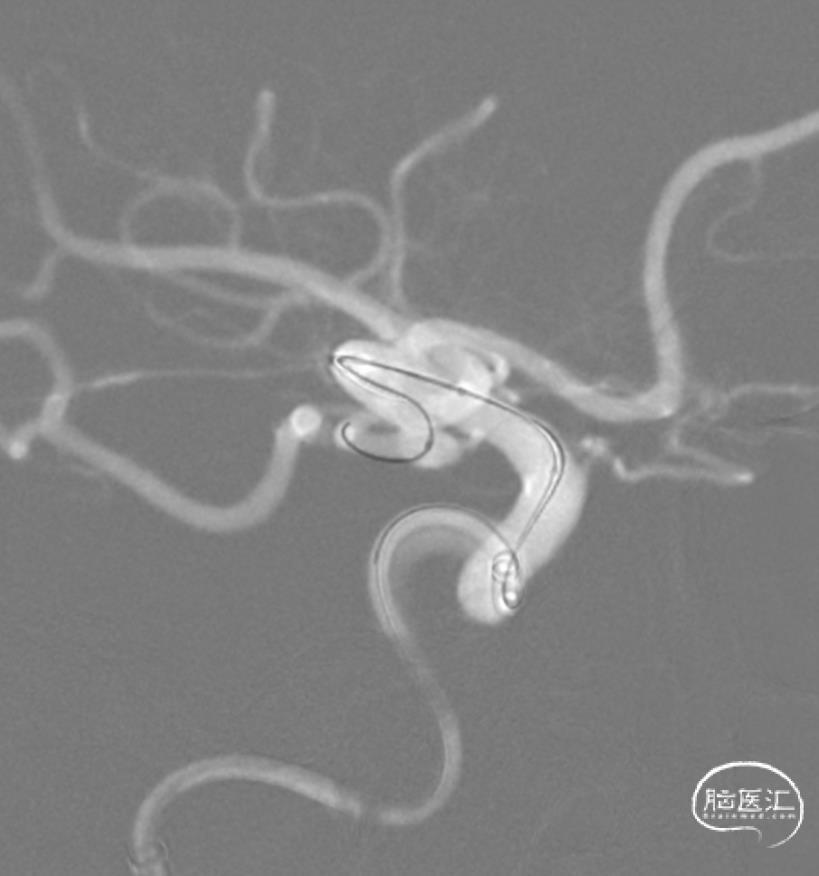

释放支架。

支架整个打开过程还是相当丝滑的。

SL-10穿网眼到达另一分支,备用。

弹簧圈栓塞。

造影分支血管良好。